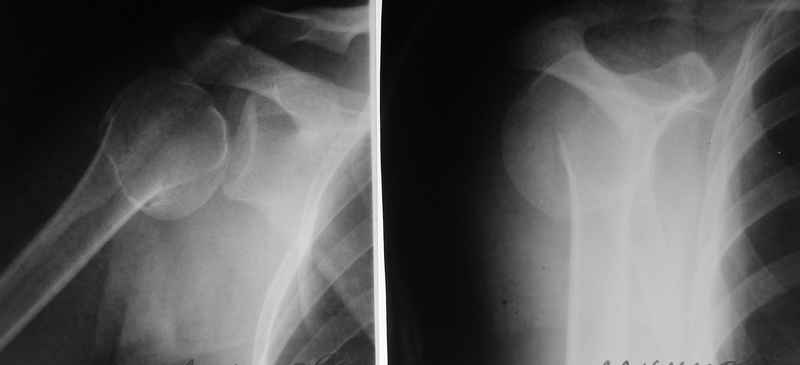

По Neer операцию рекомендовали только тогда, когда угол между диафизом и головкой составляет около 45 градусов, и переломы с меньшим углом смещения считали благоприятным для функционального результата.

Хотя "варусная импакция" в проксимальном отделе плеча срастается хорошо консервативными мерами, но в результате при восстановлении такие больные теряют часть отведения, и тем более у больной варус осложнен еще сгибанием.

Закрытые репозиции без фиксации из-за вторичного смещения неэффективны, поэтому рекомендуется репозиция с фиксацией. Методик много, кто чем владеет и отдает предпочтение закрытые-открытые, перкутанные, с блокирующими пластинами, гвоздь, множественными спицами или методом спиц по Лазареву, и осторожно с манипуляциями из=за возможности повреждения аксиллярного нерва - частый вид осложнении.